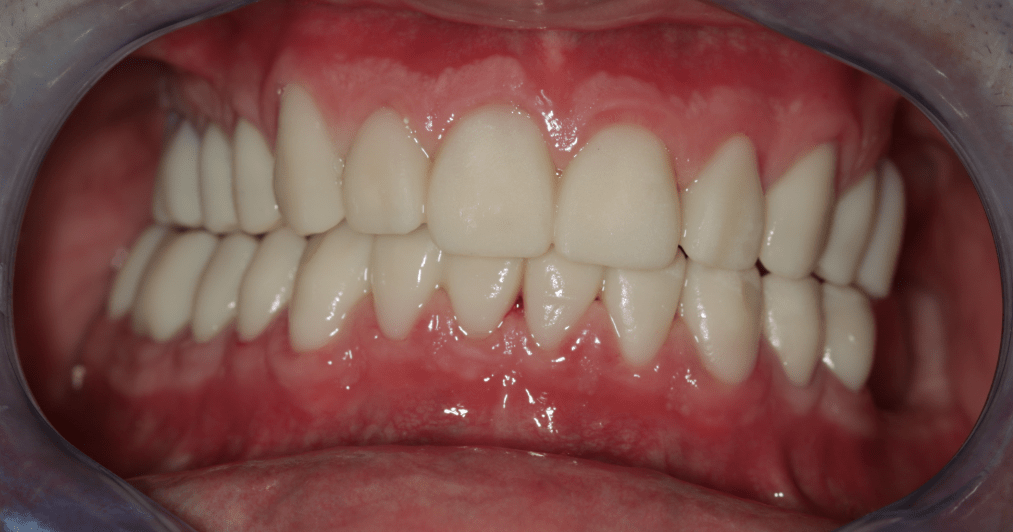

Miután a pácienssel megbizonyosodtunk a pótlás funkcionalitásának sikerességéről, készre kértük a fogtechnikai laborból azt a cirkóniumpótlást, amely a kisebb korrekciókon átesett ideiglenes pótlás tökéletesen pontos mása lett.

A páciens az elért eredménnyel mind funkcionálisan, mind esztétikailag azóta is maximálisan elégedett.